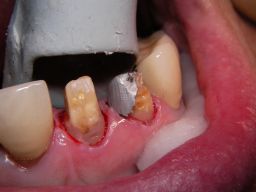

Weil auch die anderen Schneidezahnkronen (12-22) durch Randreparaturen und den schlechten Randschluß erneuerungsbedürftig aussahen, wurden 4 Einzelkronen geplant. Vorher hieß es aber noch, die schlechte Wurzelfüllung im Zahn 12 (Röntgenbild links) besser zu machen. Hierfür wurden am 17.2.06 die alten Kronen 11 und 12 entfernt. Rechts das Bild nach Entfernung von alten Füllungen und Karies. | |

Links nach Wurzelfüllung beim Einpassen des Titanstiftes. Rechts dann der schon provisorisch beschliffene Amalgamaufbau im Zahn 12. |